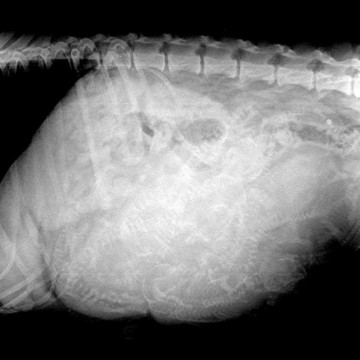

Um sicher zu sein, wie viele Welpen uns erwarten werden, fuhr ich morgens noch in die KLinik zum Röntgen. Ein tolles Bild :) "1,2,3,4,5,6,7,8... also, das ist hier müssig, ich würde sagen 8+"" waren die Worte des Tierarztes. Also fuhren wir nach Hause und warteten.